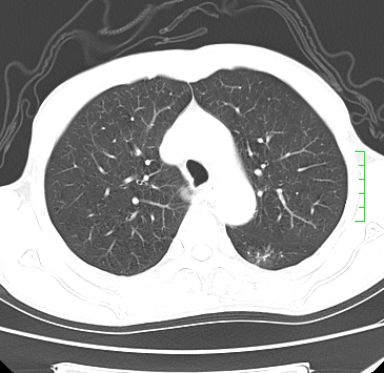

m,73y。膝关节疼痛伴双下肢水肿。入院常规胸片发现结节灶。增强为静脉期。

考虑周围型肺癌  ,双上肺结核。

肿块周围可见局限性气肿,考虑肺癌可能性大。双肺上叶继发型肺结核。

周围性肺癌    肺结核

1)考虑右肺下叶周围型肺癌。2)右肺上叶及左肺感染性病变(结核可能)。3)肺气肿。4)冠状动脉钙化。